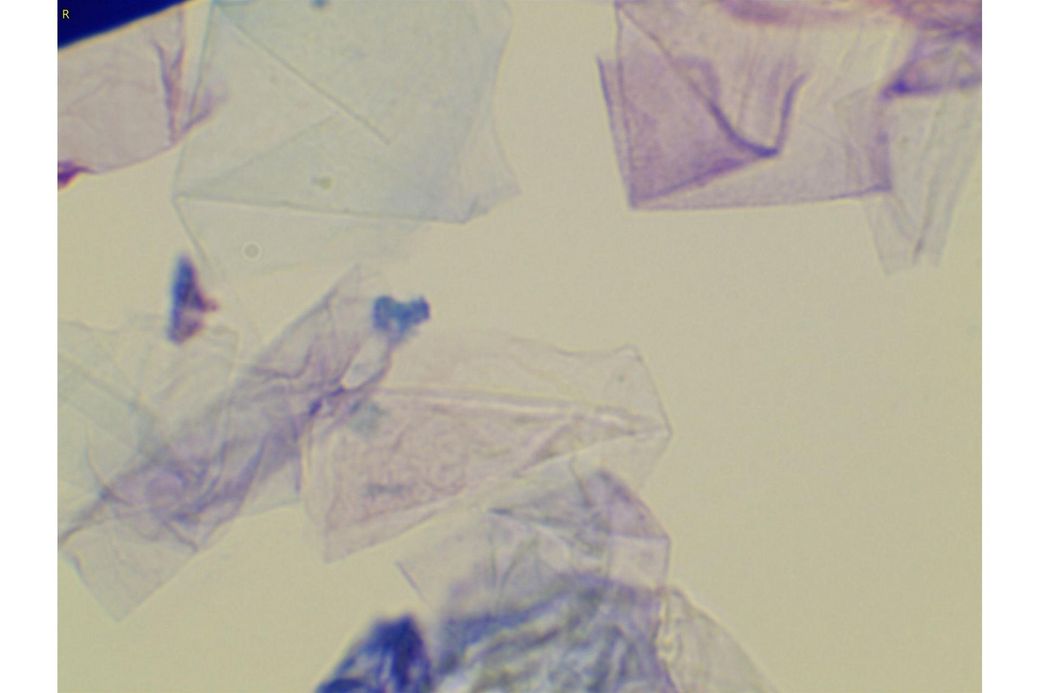

오늘 낮과 방금 5분전에 일어난 일인데요.. 강아지 귀질환 중에.. 옷입히고나서 귀를 바닥에 대고 비비거나, 귀에 통증을 호소하면서 잠깐 비틀비틀 걷는 경우 이런 경우 대체 뭘까요? 외이염일때도 이럴수도 있을까요? 아니면 중이염 내이염일지.. 한 2~3분정도 통증을 호소하다 지금은 또 정상이 됬는데 옷입을때만 옷의 목카라 부분이 귀에 닿을때 문제가 되는 느낌입니다. 평상시엔 가끔 양쪽 귀를 긁거나 귀를 자주 터는 정도입니다. 특이사항은 오른쪽귀 솜 돌돌 말아 귀안에 넣어줘도 비명을 지르며 엄청 아파하는데(작년11월경) 왼쪽은 안아파합니다)

그리고 용종이라고 코멘트 달아주셔서 저 검이경 사진 찍은곳에 물어보니 용종은 아니라고합니다.

저 부분 용종 아니라합니다